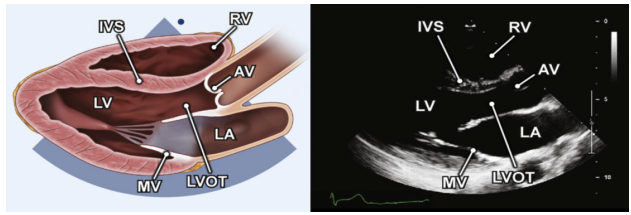

我们在胸骨旁长轴切面或胸骨上窝切面评估主动脉。在胸骨旁长轴切面的示意如图1所示,在胸骨上窝切面如图2所示。